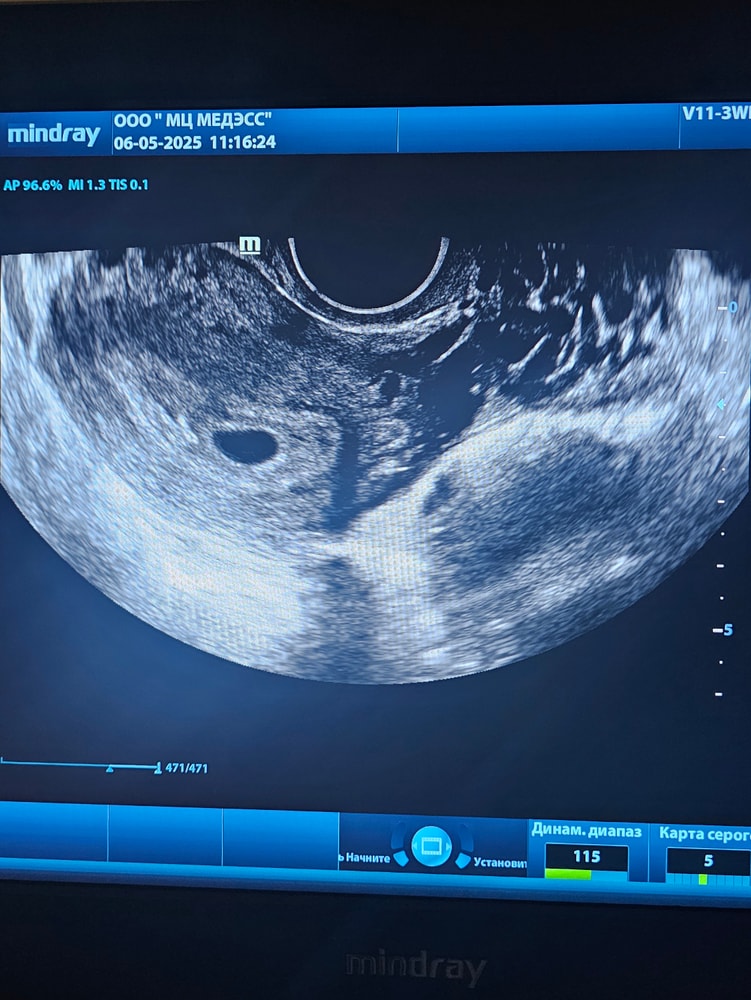

недели не эмбриона

4 5 недели не эмбриона 146 фото